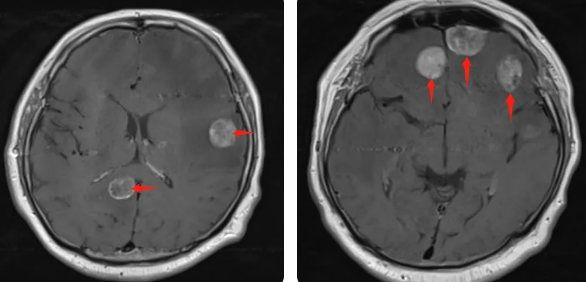

無獨有偶,60歲的左肺癌患者石先生,在外院接受了手術治療,結果術后10月出現(xiàn)腫瘤腦轉移,頭部增強MRI顯示:顱內(nèi)多發(fā)占位性病變伴水腫,接二連三的重擊讓石先生出現(xiàn)表情淡漠,沉默寡言,絕食等抑郁癥狀,VMAT放療技術與心理疏導雙管齊下,3周的治療后顱內(nèi)轉移病灶顯著縮小,部分甚至消失,困擾石先生的頭痛、頭暈癥狀也不復存在,石先生重拾對生活的希望,也對未來的治療充滿信心。